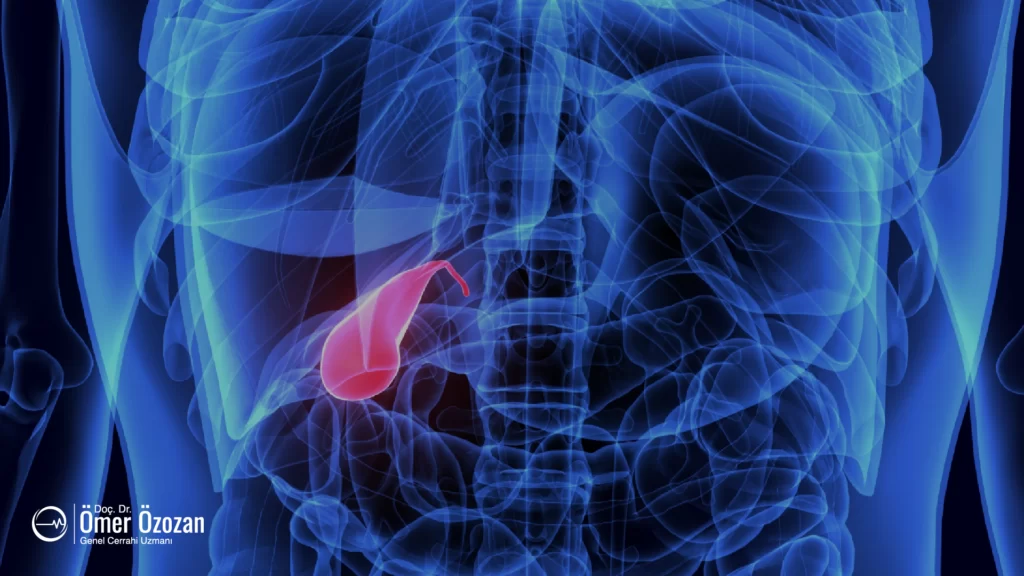

Safra Kesesi Polipleri

Safra kesesi polipleri, safra kesesinin iç yüzeyinde oluşan küçük, genellikle iyi huylu (benign) büyümelerdir. Polipler, safra kesesinin mukoza tabakasından kaynaklanır ve çeşitli tiplerde olabilir. En yaygın polip türleri arasında kolesterol polipleri, adenomlar ve iltihaplanmaya bağlı polipler bulunur. Kolesterol polipleri, safra kesesindeki kolesterol birikiminden kaynaklanır ve genellikle küçük ve iyi huyludur. Adenomlar ise daha nadir görülür ve potansiyel olarak kansere dönüşme riski taşırlar. Poliplerin büyük çoğunluğu zararsızdır ve genellikle rastgele yapılan ultrasonlar sırasında keşfedilir.